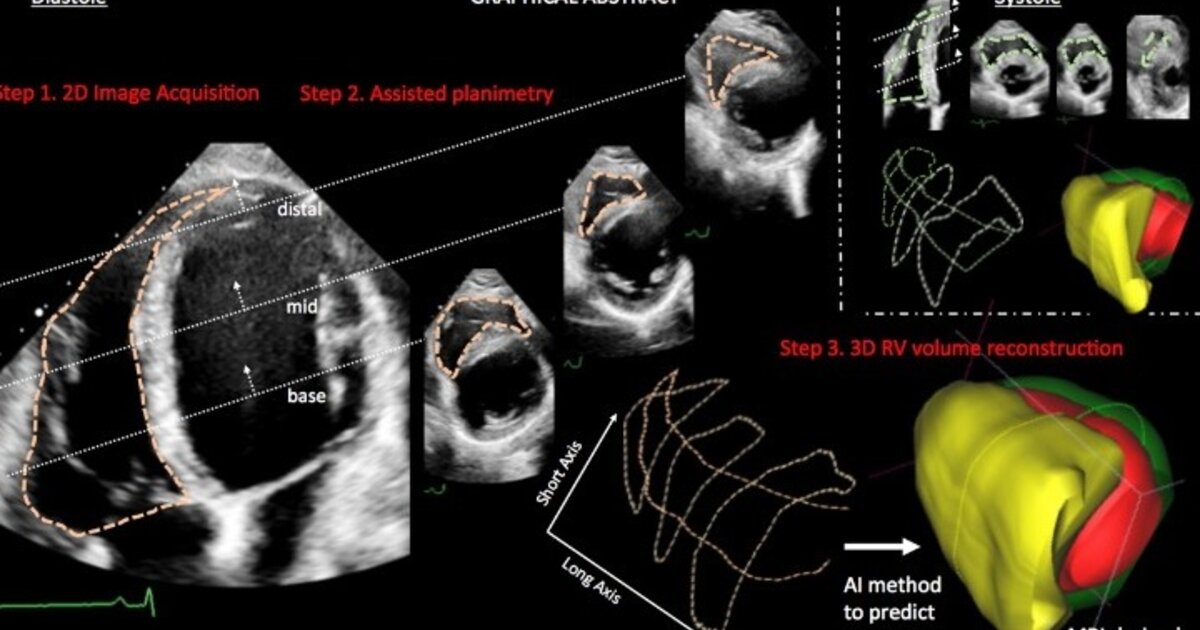

Ένα νέο λογισμικό που αξιοποιεί Τεχνητή Νοημοσύνη για να αξιολογήσει τη λειτουργία της δεξιάς κοιλίας της καρδιάς με τη βοήθεια των δεδομένων που παρέχει ο απλός δισδιάστατος υπέρηχος καρδιάς ανέπτυξαν δύο Έλληνες ερευνητές στο Κέντρο Έρευνας Τεχνητής Νοημοσύνης «Αρχιμήδης», ο επεμβατικός καρδιολόγος, πρώην επίκουρος καθηγητής Καρδιολογίας στο αμερικανικό πανεπιστήμιο Κολούμπια, Πολύδωρος Καμπακτσής, και ο επίκουρος καθηγητής Επιστήμης Δεδομένων στο βρετανικό πανεπιστήμιο Nottingham Trent, Αρχοντής Γιαννακίδης. Η εφαρμογή δοκιμάζεται για πρώτη φορά ευρέως σε κλινική έρευνα στην Ελλάδα, στο Ωνάσειο Νοσοκομείο.

«Πρόκειται ουσιαστικά για μια νέα μέθοδο που στοχεύει να αποτελέσει ένα καθημερινό εργαλείο αντικειμενικότερης και ορθότερης εκτίμησης της δεξιάς κοιλίας με χρήση του απλού δισδιάστατου υπέρηχου. Ζητά από τον καρδιολόγο να πραγματοποιήσει κάποιες μετρήσεις και στη συνέχεια στηρίζεται σε έναν αλγόριθμο Τεχνητής Νοημοσύνης για να παράξει τα αποτελέσματα», εξηγεί στο ΑΠΕ-ΜΠΕ ο Πολύδωρος Καμπακτσής.

Όπως περιγράφει στο ΑΠΕ-ΜΠΕ ο Δημήτρης Αυγερινός, στην ελληνική κλινική μελέτη θα συμμετάσχουν 200 ασθενείς. Οι ασθενείς υποβάλλονται σε δισδιάστατο υπέρηχο καρδιάς και σε μαγνητική τομογραφία καρδιάς. Το λογισμικό αξιοποιεί τα δεδομένα του υπερήχου και παράγει αποτελέσματα, τα οποία προσεγγίζουν αυτά της μαγνητικής τομογραφίας- η τελευταία χρησιμοποιείται και για τον έλεγχο της ακρίβειας της εφαρμογής.